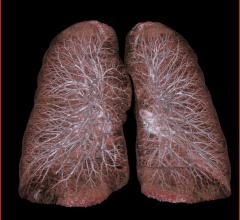

Previous evidence, including published National Lung Cancer Screening Trial (NLST) results, shows that computed…